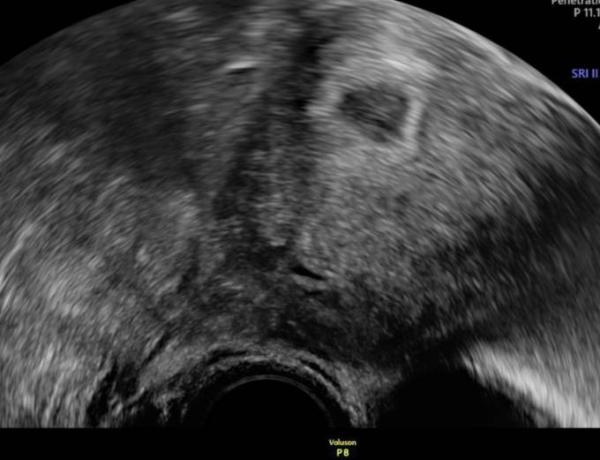

Heute war ich zum ersten Termin , sie wollte mich so früh sehen wegen Schilddrüse, zur Blutabnahme usw. Sie sagte soweit sieht alles super aus und das man noch nicht mehr sieht wie auf dem Foto sei auch völlig normal , darf vor Weihnachten noch mal kommen

Bild zu Heute Termin bei 5+2 - Forum für Juli - Mamis

Mein nächster Termin ist der 14.12 , danach ist dann ja erstmal Weihnachten und Jahresende und dann im Januar wieder . Ich finde meine Fruchthöhle ist gar nicht so schön rund , sehe immer nur Bilder wo sie so schön rund ist.